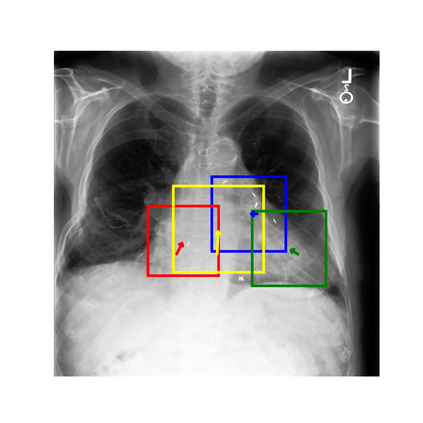

To address these issues, we propose a novel Adaptive patch-word Matching (AdaMatch) model to correlate chest X-ray (CXR) image regions with words in medical reports and apply it to CXR-report generation to provide explainability for the generation process. AdaMatch exploits the fine-grained relation between adaptive patches and words to provide explanations of specific image regions with corresponding words. To capture the abnormal regions of varying sizes and positions, we introduce the Adaptive Patch extraction (AdaPatch) module to acquire the adaptive patches for these regions adaptively. In order to provide explicit explainability for CXR-report generation task, we propose an AdaMatch-based bidirectional large language model for Cyclic CXR-report generation (AdaMatch-Cyclic). It employs the AdaMatch to obtain the keywords for CXR images and `keypatches' for medical reports as hints to guide CXR-report generation. Extensive experiments on two publicly available CXR datasets prove the effectiveness of our method and its superior performance to existing methods.